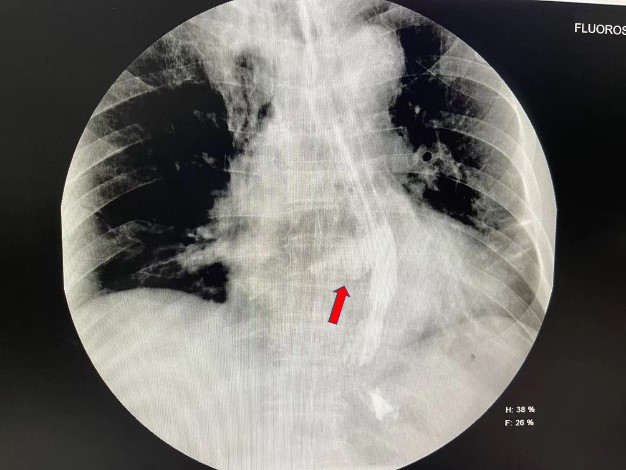

“单纯的纵隔气肿很少这么快引起胸腔积液和肺不张,难不成是吞咽粽子时造成的食管破裂?不行,要马上进行食管造影!”李辉当机立断。检查结果中,只见患者食管下段造影剂自食管右侧壁一条大约3cm长的破口渗漏至右侧纵隔,果然是食管破裂。

食管造影提示食管破裂。通讯员供图